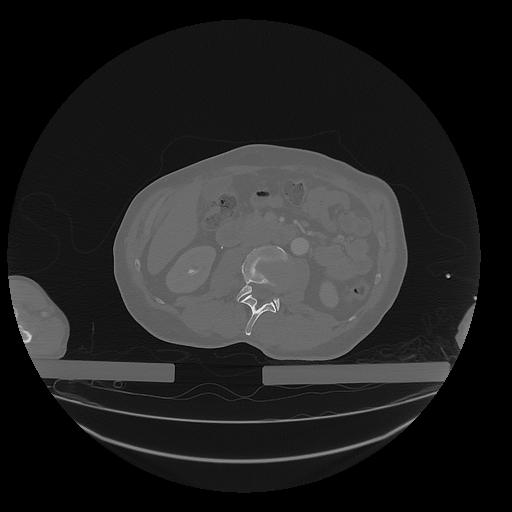

31 PULMON,CE,Vol,1.0,PULMON,,